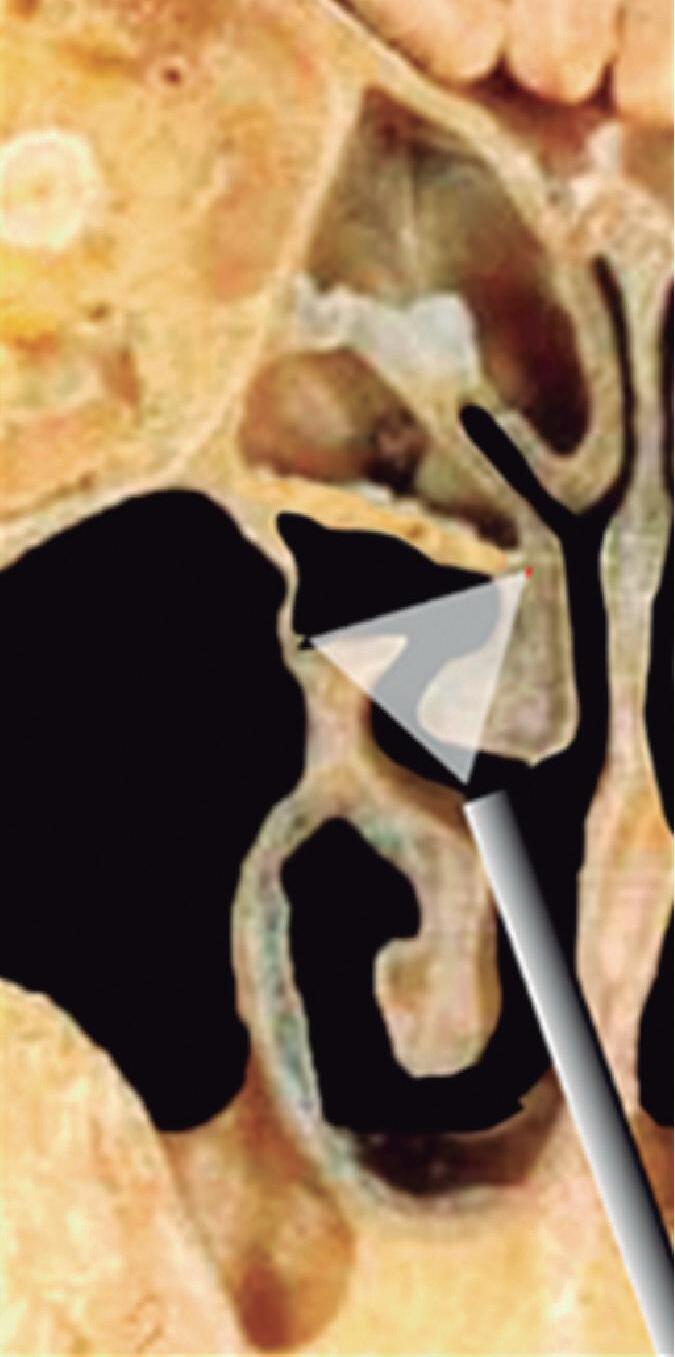

1-13. Montagem em aspecto endoscópico e peça anatômica (Bagatella) demonstrando a relação do processo uncinado e bulha etmoidal com a parede medial da órbita: (1) porção meatal da concha média; (2) processo uncinado; (3) bulha etmoidal; (4) parede medial da órbita.

1-16. Relação da bulha etmoidal com a órbita em corte axial, coronal e sagital, respectivamente.

A bulha etmoidal lembra a forma de uma meia-lua e se encaixa na parede medial da órbita (lâmina papirácea) criando, posterossuperiormente (em sua relação com a porção vertical da lamela basal), um recesso algumas vezes chamado de seio lateral e outras de recesso suprabulhar, onde se abrem a própria bulha e cavidades etmoidais vizinhas.